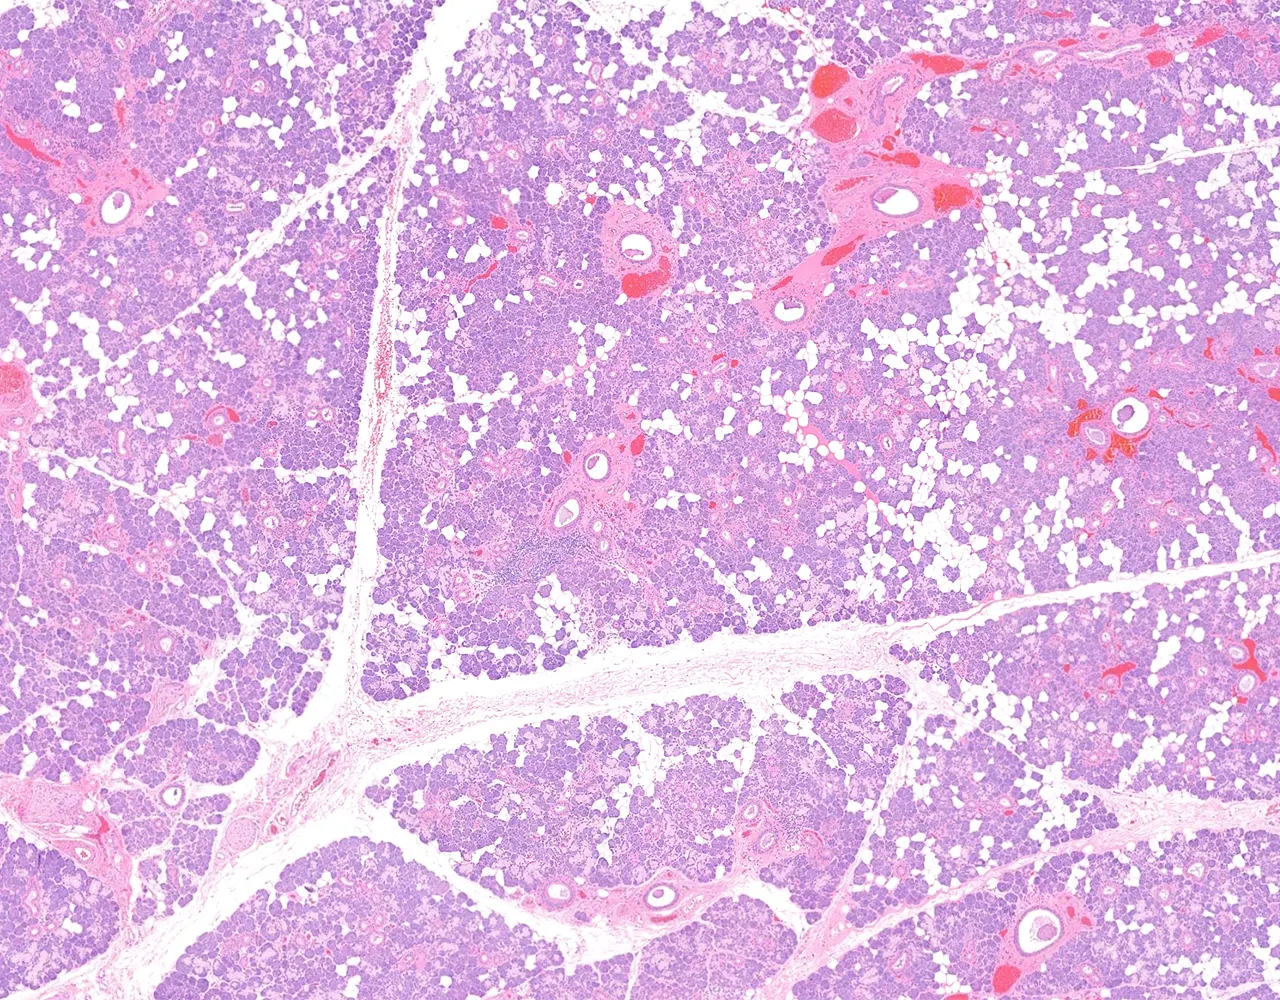

- Each gland is surrounded by a thin capsule.

- The capsule extends septa into the glandular parenchyma, dividing it into lobes and lobules.

- Microscopically, the functional structure of a salivary gland consists of secretory acini and a duct system.